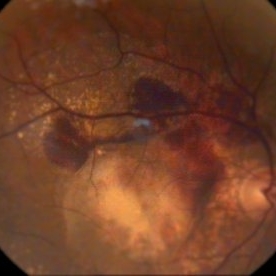

Myopic Degeneration, Macular Hemorrhage

Sep 10 2014 by Mehul A Shah

A 50-year-old male patient presented with complaint of sudden loss of vision.

Photographer: Drashti Netralaya,Dahod

Imaging device: FF 450

Condition/keywords: myopic degeneration